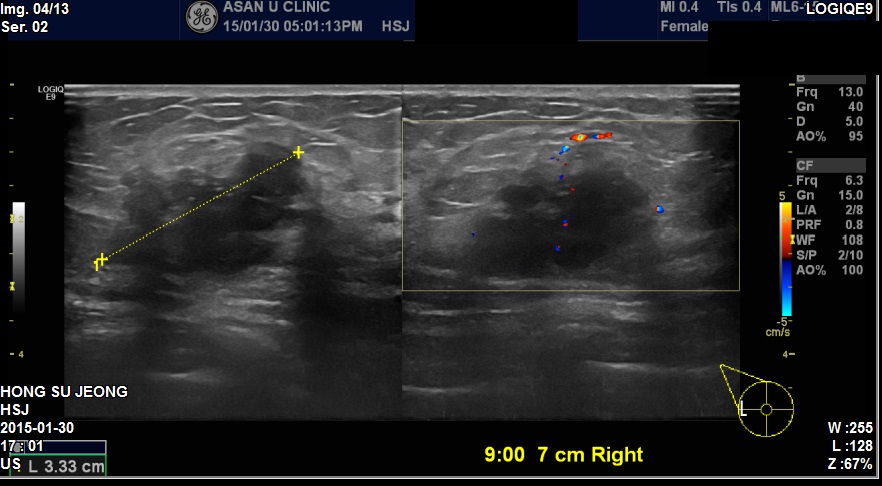

우측겨드랑이에 만져지는 멍우리로 내원하신 37세 환자분이십니다

본원에서 우측유방에 3.3cm 혹과 겨드랑이에 만져지는 혹 조직검사 시행하였고

결과상 침윤성 유관암과 겨드랑이 림프절까지 전이된 상태였습니다.